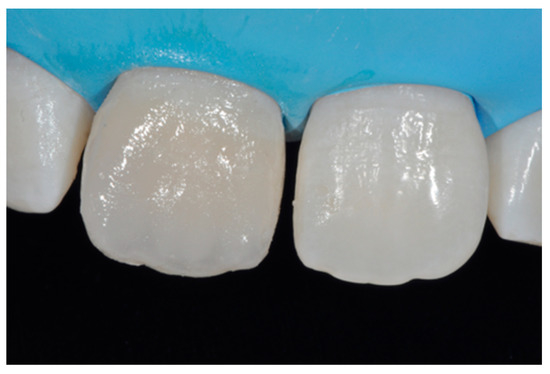

Figure 27.

Clinical situation after polishing procedures. Reprinted from Restauri diretti nei settori anteriori, G. Paolone, S. Scolavino, © 2021, with permission from Quintessence Publishing Italy.